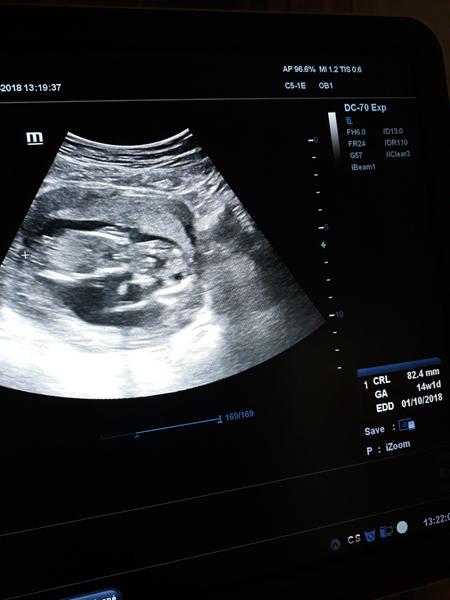

Ahoj děvčata, vy tady tak hezky diskutujete 😍, tak se připojím. Jsem nyní na konci 14 tt. Screening mi nedopadl moc dobře. Utz byl Ok, ale celkově prý snad kvůli věku. A to mám embryo vyšetřené před transferem. Odebrali mi krev a teď 14 dní čekat na výsledky . Trochu jsem si prohrála s fotečkou na oznámení. 😃

@rosalline ahoj snad dobre.Pred mesicem sem byla na utz a vse ok.Fazolka krasne roste.Ted jdu ve ctvrtek po mesici opet.Tak uvidime jestli uz bude neco videt.Aby jsme vedely co to bude☺Jinak nic mi neni...takze je asi vse v poradku...a ro je hlavni.A co ty?